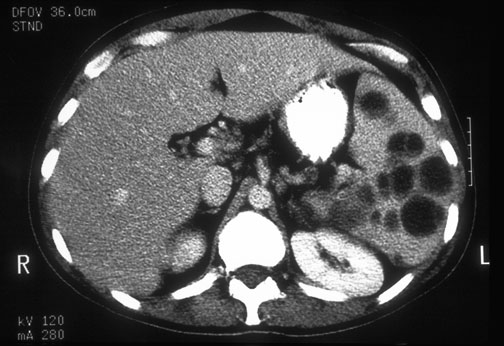

| The enlarged spleen with the rounded areas of lucency seen here in a patient with the acquired immunodeficiency syndrome represent masses of the foamy exudate typical for Pneumocystis carinii (jirovecii). This infection uncommonly disseminates from the lung. |